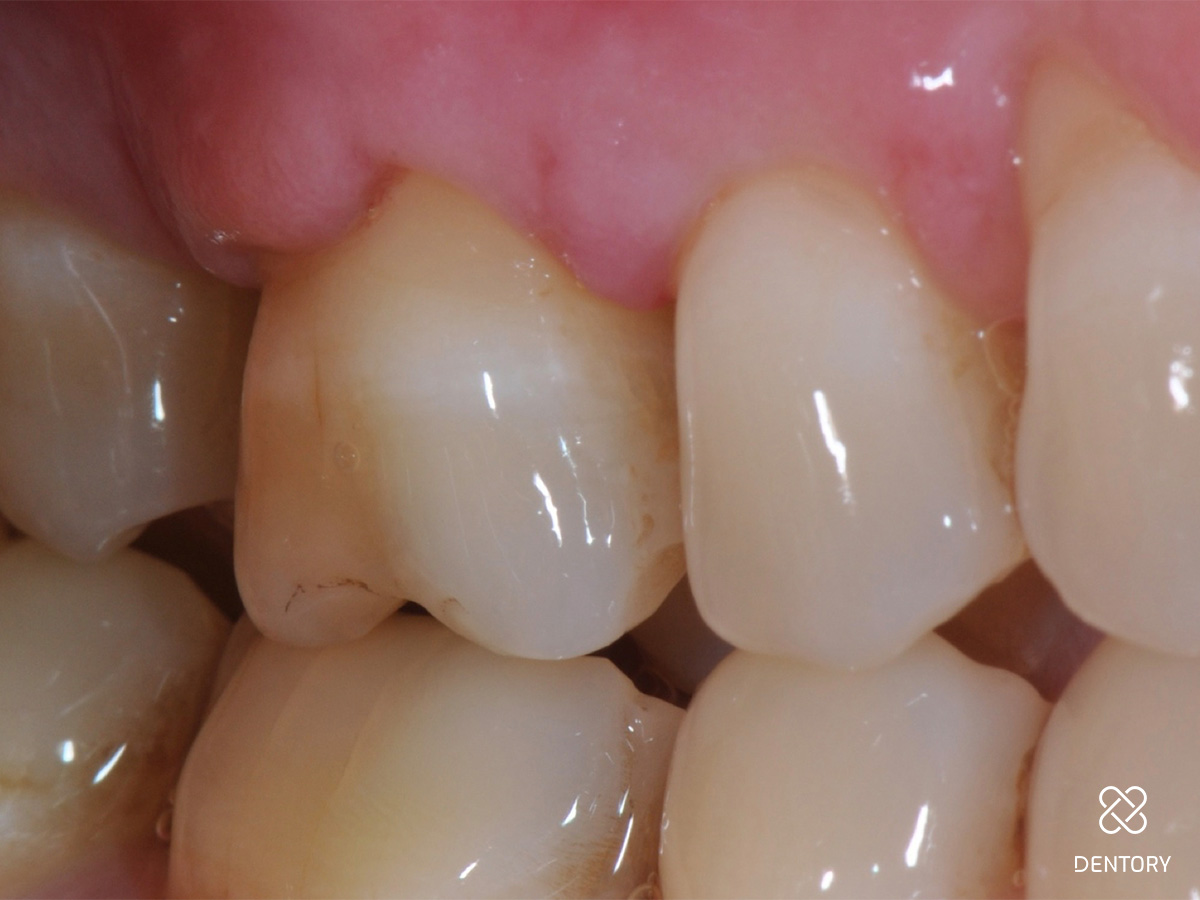

Abbildung 2

Die Ausgangssituation der regio 16/17. Hier wurden initial Sondierungstiefen von 9 und 11 mm mesial an Zahn 17 gemessen.